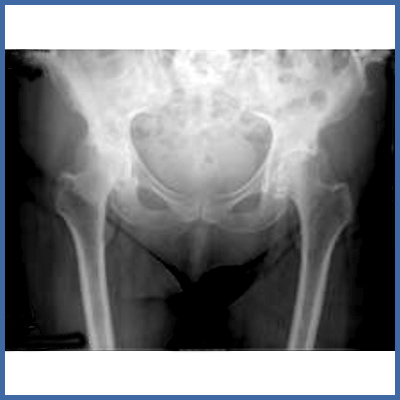

Ist die Abnutzung des Gelenkknorpels schon so weit fortgeschritten, dass ein Gelenkserhalt nicht mehr möglich ist, muss das Gelenk ersetzt werden. Man spricht in diesem Stadium von einer Arthrose.

Das Röntgenbild links zeigt bereits eine ausgeprägte Gelenkspaltverschmälerung und Deformierung der Gelenkfläche.